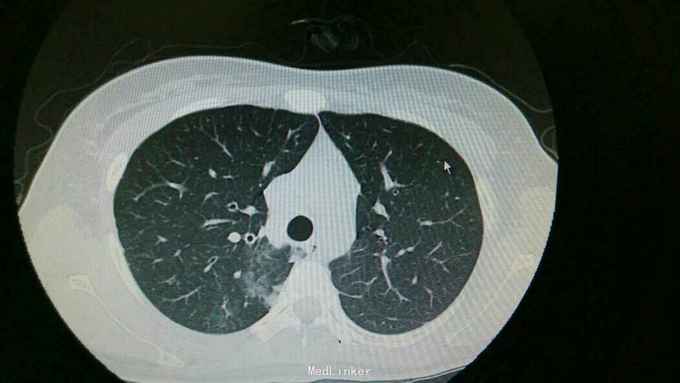

查体:双肺呼吸音粗,右肺可闻及湿罗音, 余无特殊 辅查:血常规示中性粒细胞稍高。胸片:右上肺野炎性病变。肺炎支原体抗体滴度1:640。胸部CT:双肺炎症。

诊断:支原体肺炎。 治疗,予以阿奇霉素抗感染,止咳化痰等处理。复查胸片提示炎症较前好转。

讨论+随访:临床支原体肺炎为不典型肺炎,其诊断主要依靠支原体抗体滴度及影像学检查。一般治疗一个星期可好转。